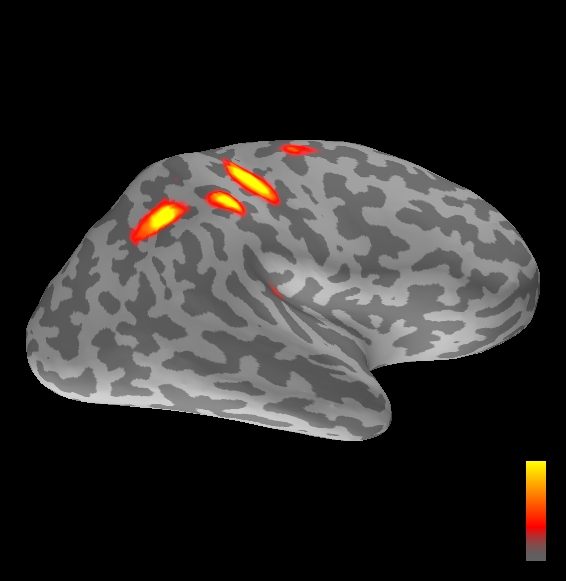

5.2 Results

We applied the ASMC sampler to MEG topographies taken from the above recordings by selecting specific time points according to the previous analysis; the parameter values in the algorithm were the same as those used for the analysis of synthetic data, with the only exception of the noise standard deviation , here estimated from the pre–stimulus interval. In order to validate the results of the ASMC, we also computed source estimates using three other methods: a PF, that approximates the posterior distribution for the current dipoles conditioned on the data up to the selected time point; dSPM, which is based on a distributed source model with an –prior, and consists in normalizing the Tikhonov regularized solution by the noise standard deviation; and sLORETA, which is similar to dSPM but is claimed to have a smaller localization bias. Figure 4 shows the results at , and ms after the stimulus onset. The results are visualized on a computer representation of the brain obtained by “inflating” the cortical surface: gray levels contain the anatomical information, light gray representing gyri and dark gray representing sulci; the activity estimate is coded in color scale, increasing from red to yellow. Importantly, this visualization allows activity in the sulci to be clearly visible; on the other hand, since neighbouring volumes may be moved apart by the inflation process, distinct activity regions are often due to underlying volumetric masses that are very close to each other.

Before describing the results, let us comment on the qualitative difference between the images produced by the ASMC sampler and the PF, on the one hand, and those produced by dSPM and sLORETA, on the other. First of all, we point out that all the quantities shown in the images of Fig. 4 are somehow related to the probability of activation at specific locations. Indeed, for both the ASMC and the PF we plot the approximation of the intensity measure (3.8); for any single grid point, this value can be interpreted as the probability of a dipole being at that location, while it integrates, over a given volume , to the mean number of dipoles within . As for dSPM, the represented quantity is a statistical value that is –distributed under the null–hypothesis of zero activity; as a direct consequence, it also yields a probability of activation, which is however not constrained to be dipolar. Similar considerations apply to sLORETA, although with a different statistical distribution. Importantly, the representation of the results is clearly affected by the setting of the visualization threshold. Owing to the explained differences between the methods, it seems reasonable to use a different value for each method. At the same time, since the plotted quantity is a probability of activation, it seems right to use the same thresholding for different time points. In this connection, the thresholds in Fig. 4 have been chosen by hand following the guidelines just outlined.

Using the same thresholding and parameters at different time points makes the four methods respond differently to the diverse intensities of the different sources. Whenever a stronger source is active, both sLORETA and dSPM will tend to produce widespread estimates, while weaker sources will be represented as small active areas. The behaviour of the ASMC and of the PF is the opposite: a stronger signal will lead to a precise localization of a dipolar source, and then to a focal marginal distribution for the location; a weaker signal will translate to higher uncertainty on the source position, and therefore a more widespread posterior map.

The phenomenon just described is indeed clearly visible in Figure 4. At ms, all the methods correctly identify the rather strong activation in the contra–lateral primary somatosensory cortex: the ASMC and the PF provide very focal maps, while dSPM and sLORETA provide compatible widespread estimates; dSPM also exhibits a more posterior peak which does not fit with the commonly agreed models of the response to median nerve stimulation; this may be due to the formerly described brain inflation.

At ms, the ASMC localizes two sources, one in the right hemisphere and a weaker one in the left hemisphere; these sources appear to be compatible, for timing and location, with the Posterior Parietal Contra and Parietal Opercular Ipsi described in Mauguiere et al. (1997). The PF finds the very same source in the right hemisphere, but it estimates no dipoles in the left one. Such discrepancy between these two methods, which are based on the same source model, is possibly due to two facts: first, thanks to its iterative nature, the ASMC is likely to explore the state space more thoroughly and is therefore more suited to identify weak sources; second, the log–uniform prior on the strength of the dipole moment in the ASMC has a wider range than the corresponding Gaussian prior in the PF. Slightly different results are provided here by dSPM and sLORETA. The activity estimate computed by dSPM seems very similar to that of ms, having the same spatial distribution with a weaker intensity. The estimate of sLORETA in the right hemisphere includes that of the ASMC and of the PF. Neither dSPM nor sLORETA find significant activity in the left hemisphere.